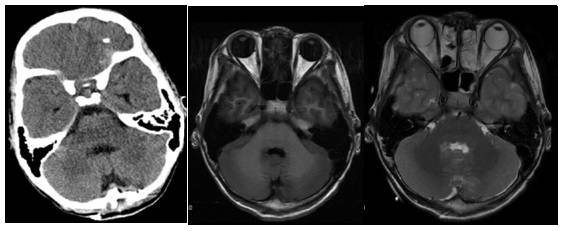

辅助检查:MRI平扫加增强显示第四脑室内可见不规则肿块影,T1WI呈高低混杂信号,T2WI呈混杂低信号,增强扫描可见不均匀强化,大小约36x25.7x51.1mm,脑桥延髓后部及小脑蚓部受压。诊断“第四脑室肿块,室管膜瘤?”(图1)。

图1. MRI检查:第四脑室内可见不规则肿块影,T1WI呈高低混杂信号,T2WI呈混杂低信号,增强扫描可见不均匀强化,脑桥延髓后部及小脑蚓部受压。